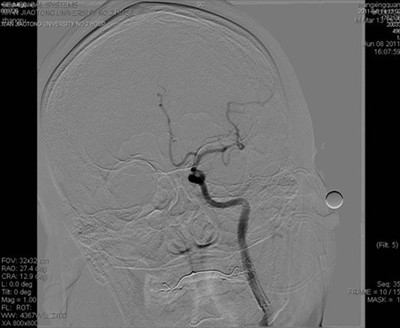

图3 正位片:左侧颈内动脉血管内狭窄部位支架成形术后,血管通畅

患者送入我院时意识模糊,右侧肢体完全不能移动,不能言语,我院神经内科按照脑梗死应急预案,通过急性脑梗死绿色通道立即行头颅CT排除脑出血。考虑脑梗死,但病灶尚未显示,有急诊动脉介入治疗的指证和时间。吴海琴主任和张桂莲副主任立即向家属谈病情并介绍介入治疗的利弊,同时展淑琴副主任医师和卜宁及孙宏主治医师指导完成术前各项准备工作并加用基础治疗。家属了解病情后签字同意介入治疗。吴海琴主任、张桂莲副主任、张茹副主任医师立即在祁小江技师、赵菊凤护士的配合下给患者行脑血管造影,造影见左侧颈内动脉内有异常混杂密度团块影,并局部重度狭窄,远端血管血供极差,考虑血栓形成所致狭窄。虑及动脉溶栓有可能使血栓脱落,栓塞远端血管,遂在保护伞的保护下给局部狭窄部位安放2枚支架,把血栓压住贴壁,使狭窄的颈内动脉基本恢复正常,远端血供恢复,患者意识清楚,右侧肢体能够在床头移动。此时距离患者发病仅4小时。今晨患者右侧肢体能够抬离床面并对抗阻力,能连续说出数个单词。